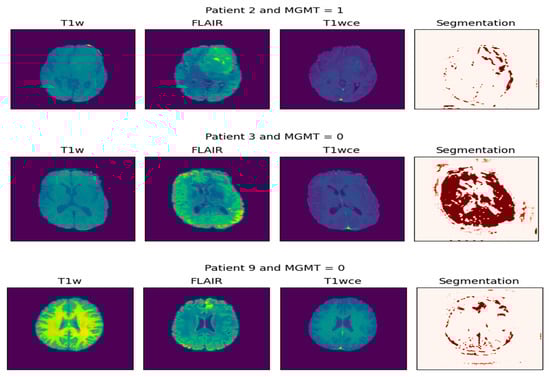

This process is visualized in Figure 4. The left panel displays the multi-parametric input, consisting of the original T1-weighted (T1W), FLAIR, and contrast-enhanced T1-weighted (T1wce) MRI sequences. The right panel presents the corresponding segmentation mask, where the tumor region is highlighted in red. This visualization effectively isolates the pathological area, providing a critical foundation for volumetric analysis, diagnostic confirmation, and subsequent treatment planning. Together, these panels demonstrate the initial step of non-invasively extracting a tumor’s spatial profile from multi-parametric MRI data.

Figure 4. Extraction of tumor biopsy (the result of segmentation).